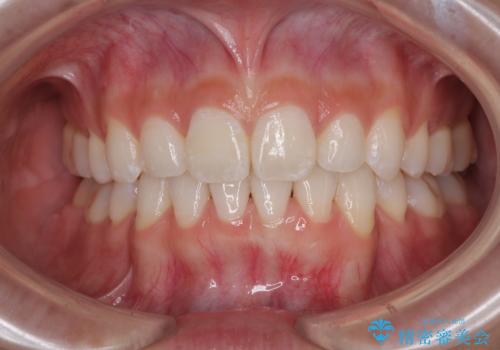

下唇に前歯が当たって跡が残ってしまう状態でしたが、スッキリとした口元に仕上げることができました。